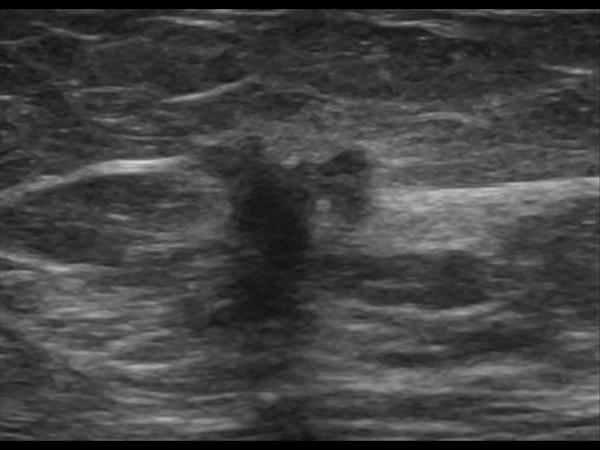

Ung thư vú - Ảnh 3

Ung thư vú

» Thông tin: Nữ giới – 71 tuổi.

» Lâm sàng: Khối tuyến vú.